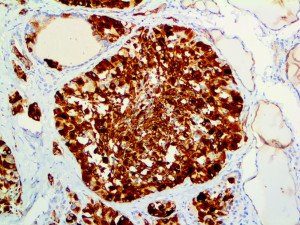

It is the ICU physician who is most likely to witness one of the deadliest manifestations of the abnormal immunological response, the cytokine storm syndrome (CSS). This response is also referred to by some as the cytokine release syndrome (CRS). CSS is characterized by continuous activation and expansion of macrophage and lymphocyte populations, which secrete large amounts of cytokines, causing the cytokine storm. This massive cytokine release is akin to hemophagocytic lymphohistiocytosis (HLH) disease, a syndrome characterized by initial unchecked and persistent activation of cytotoxic T lymphocytes and NK cells.

Clinical and laboratory manifestations of HLH include fever, enlarged liver and/or spleen, neurologic dysfunction, coagulopathy, liver dysfunction, cytopenias (i.e., low levels of erythrocytes, leukocytes, and/or platelets), hypertriglyceridemia, hyperferritinemia, hemophagocytosis, and eventually diminished NK cell activity as the immune system becomes progressively paralyzed. HLH can be familial (primary HLH) or secondary to another disease process (sHLH), such as rheumatic disease, in which it is referred to as macrophage activation syndrome (MAS, characterized by elevated ferritin).

This activation induces inflammatory monocytes to highly express IL-6, starting a localized and then systemic cascade effect that results in hyperproduction of IL-6, which accelerates the inflammatory process. Because IL-6 also increases vascular permeability, excessive levels cause blood vessels to become very leaky. This, along with clotting factors released from vascular endothelial cells, stimulates the coagulation cascade, resulting in microthrombosis (tiny clots), which leads to ischemia and tissue death of the kidney, intestines, heart, liver, brain and extremities.